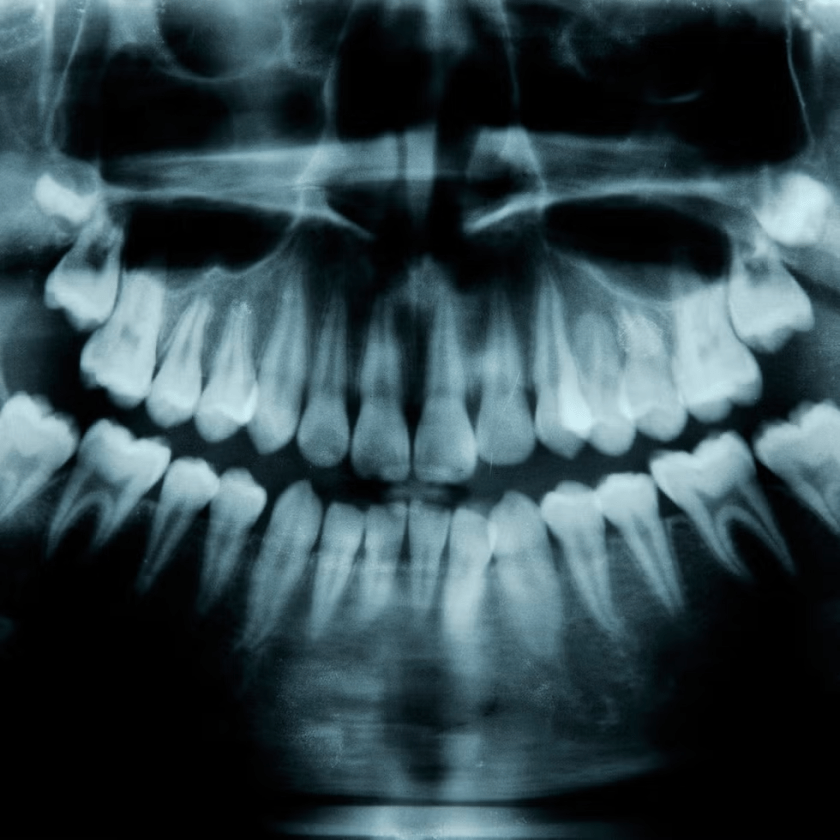

- A study out of Japan showed how targeting genes can regrow teeth in animals. Now, the team has turned to a human clinical trial.

- By targeting the USAG-1 gene, researchers believe that they can help people without a full set of teeth regrow teeth.

- The team says that humans have a third set of teeth available as buds, ready to grow as needed.

Following up on a 2021 study (published in Scientific Reports) that showed how medicine targeting the protein synthesized by the USAG-1 gene could impact the number of teeth grown in animals, the team has turned its attention to humans. In 2024, they started a clinical trial of the medicine, which they hope to have ready for general use in 2030.

Researchers found that the USAG-1 protein could limit the growth of teeth in mice, so ensuring that the protein didn’t form could potentially invite teeth to grow. The team developed a medication to block the protein, and successfully allowed mice to grow new teeth.

And that hope, Takahashi claims, should be further encouraged by the fact that we already come pre-loaded with the starting point. He said that his previous research shows that humans have the start of a third set of teeth already embedded in our mouths. This is most visibly exhibited by the 1 percent of humans with hyperdontia, the growing of more than a full set of teeth. And Takahashi believes that activating that third set of buds with the right gene manipulation could promote tooth regrowth.